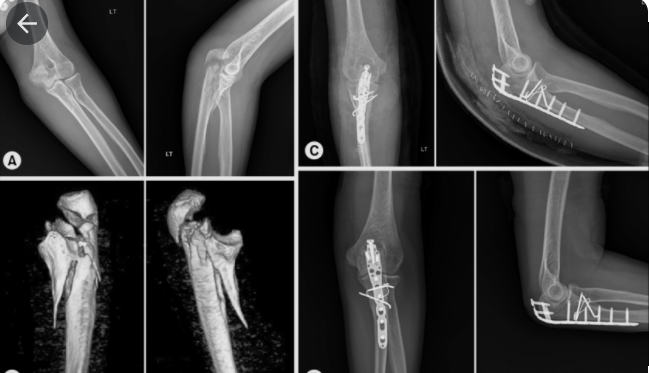

Sau đó bác sĩ sẽ cho chụp Xquang ở khuỷu tay, trên phim sẽ nhìn thấy đường gãy, có nát xương nhiều không, và có phân loại phù hợp

Phân loại

Tùy vào hình dạng ổ gãy nhìn thấy trên phim Xquang mà bác sĩ sẽ phân loại kiểu gãy thành 6 loại. Mỗi loại sẽ có cách điều trị thích ứng. Nên việc phân loại chính xác sẽ giúp điều trị chuẩn cho từng bệnh nhân cụ thể.

Điều trị phẫu thuật

Dùng cho gãy mỏm khuỷu mà ổ gãy lệch nhau

Lúc này mổ để nắn chỉnh xương lại, và kết hợp xương bằng dụng cụ. Có nhiều loại dụng cụ như:

Đinh và chỉ thép néo ép số 8

Nẹp vít chuyên dụng cho mỏm khuỷu

Đinh vít